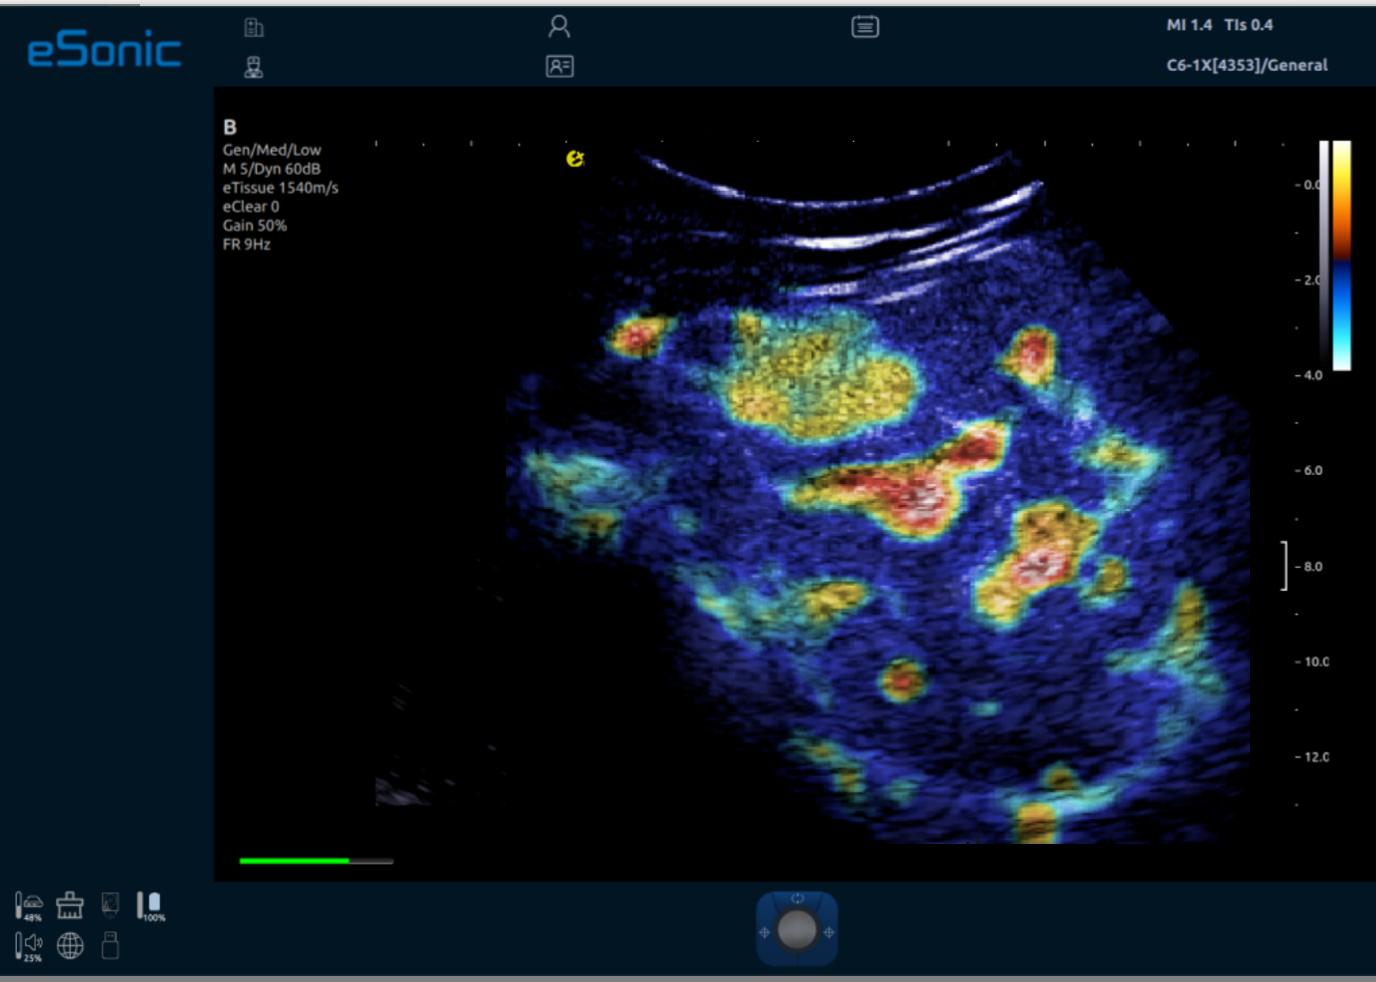

iPlane Vascular 微视血流显像

iPlane Contrast 超快速造影成像